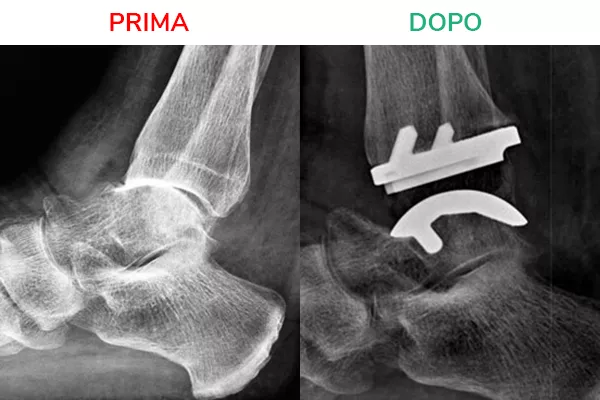

Radiografia in movimento

La radiografia in movimento mostra lo spazio articolare ripristinato e la distanza tra tibia e astragalo. Il movimento risulta fluido e scorrevole, simile a quello fisiologico. Il risultato che si deve ottenere al termine dell’intervento di Protesi di Caviglia è la normale mobilità della caviglia in flesso-estensione.